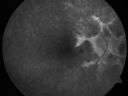

Angioid Streaks - CNVM near Fovea

OD: Vertical C/D ratio is 0.0. There is a posterior vitreous separation. There are angioid streaks with most of the streaks going nasally, but there is a streak just going off of the optic nerve at 10:00 o’clock. Adjacent to that is a triangular-shaped subretinal choroidal neovascular membrane with hemorrhage around the edges which stops a disc diameter short of the fovea.

OS: Vertical C/D ratio is 0.0. There is a posterior vitreous separation. There are, similarly, angioid streaks around the optic nerve and there is one streak which goes just superior to the fovea.

1. IDIOPATHIC ANGIOID STREAKS – BOTH EYES

2. SUBRETINAL CHOROIDAL NEOVASCULAR MEMBRANE – RIGHT EYE

3. AGE-RELATED MACULAR DEGENERATION – RIGHT EYE

4. RETINAL HEMORRHAGE – RIGHT EYE

DISCUSSION: I explained to the patient unfortunately there is a blood vessel growth in the right eye which, if left alone, has about an 80% chance of severely impairing her central vision. With intravitreal Avastin, we can reduce the risk of vision loss in that eye and probably even facilitate some vision improvement since the Avastin is excellent at shrinking up the blood vessels and drying up the leakage.

Treated with one year of avastin with good result and no vision loss.     (0 votes)